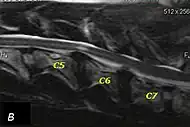

Wobbler disease is probably inherited in the Borzoi, Great Dane, Doberman, and Basset Hound.[2] Instability of the vertebrae of the neck (usually the caudal neck) causes spinal cord compression. In younger dogs such as Great Danes less than two years of age, wobbler disease is caused by stenosis (narrowing) of the vertebral canal[3] related to degeneration of the dorsal articular facets and subsequent thickening of the associated joint capsules and ligaments.[1] A high-protein diet may contribute to its development.[4] In middle-aged and older dogs such as Dobermans, intervertebral disc disease leads to bulging of the disc or herniation of the disc contents, and the spinal cord is compressed.[3] In Great Danes, the C4 to C6 vertebrae are most commonly affected; in Dobermans, the C5 to C7 vertebrae are affected.[5]

The disease tends to be gradually progressive. Symptoms such as weakness, ataxia, and dragging of the toes start in the rear legs. Dogs often have a crouching stance with a downward flexed neck. The disease progresses to the front legs, but the symptoms are less severe. Neck pain is sometimes seen. Symptoms are usually gradual in onset, but may progress rapidly following trauma.[6] X-rays may show misaligned vertebrae and narrow disk spaces, but it is not as effective as a myelogram, which reveals stenosis of the vertebral canal. Magnetic resonance imaging has been shown to be more effective at showing the location, nature, and severity of spinal cord compression than a myelogram.[7] Treatment is either medical to control the symptoms, usually with corticosteroids and cage rest, or surgical to correct the spinal cord compression. The prognosis is guarded in either case. Surgery may fully correct the problem, but it is technically difficult and relapses may occur. Types of surgery include ventral decompression of the spinal cord (ventral slot technique), dorsal decompression, and vertebral stabilization.[8] One study showed no significant advantage to any of the common spinal cord decompression procedures.[9] Another study showed that electroacupuncture may be a successful treatment for Wobbler disease.[10] A new surgical treatment using a proprietary medical device has been developed for dogs with disc-associated wobbler disease. It implants an artificial disc (cervical arthroplasty) in place of the affected disc space.[11]